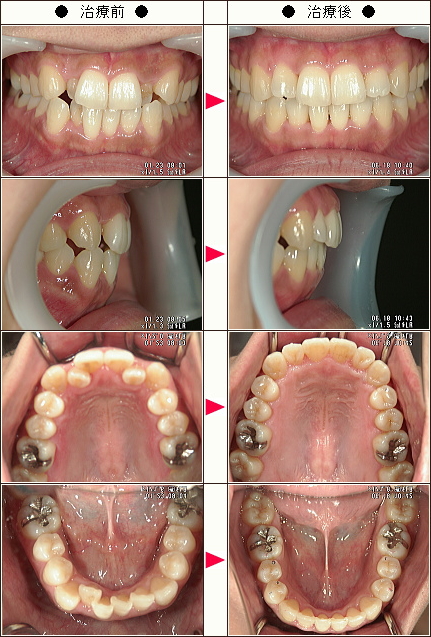

歯のデコボコ矯正症例[AYA様 31歳 女性]

| 主訴 | 上下の前歯のデコボコ |

| 治療方法 | ワイヤー6か月 マウスピース6か月 |

| 治療期間 | 12カ月 |

| 費用(税込み) | 121万円 |

| 治療等の主なリスク、副作用 | 奥歯を親知らずの方向に動かすために親知らずの抜歯は必須になります 下顎の前歯のブラックトライアングルの改善のために、下の前歯の隣接面を削りました |

| 治療詳細 | ワイヤー矯正で奥歯を外側に広げて、親知らずの方向に移動して、できたスペースを利用してマウスピースで前歯を中に入れました |